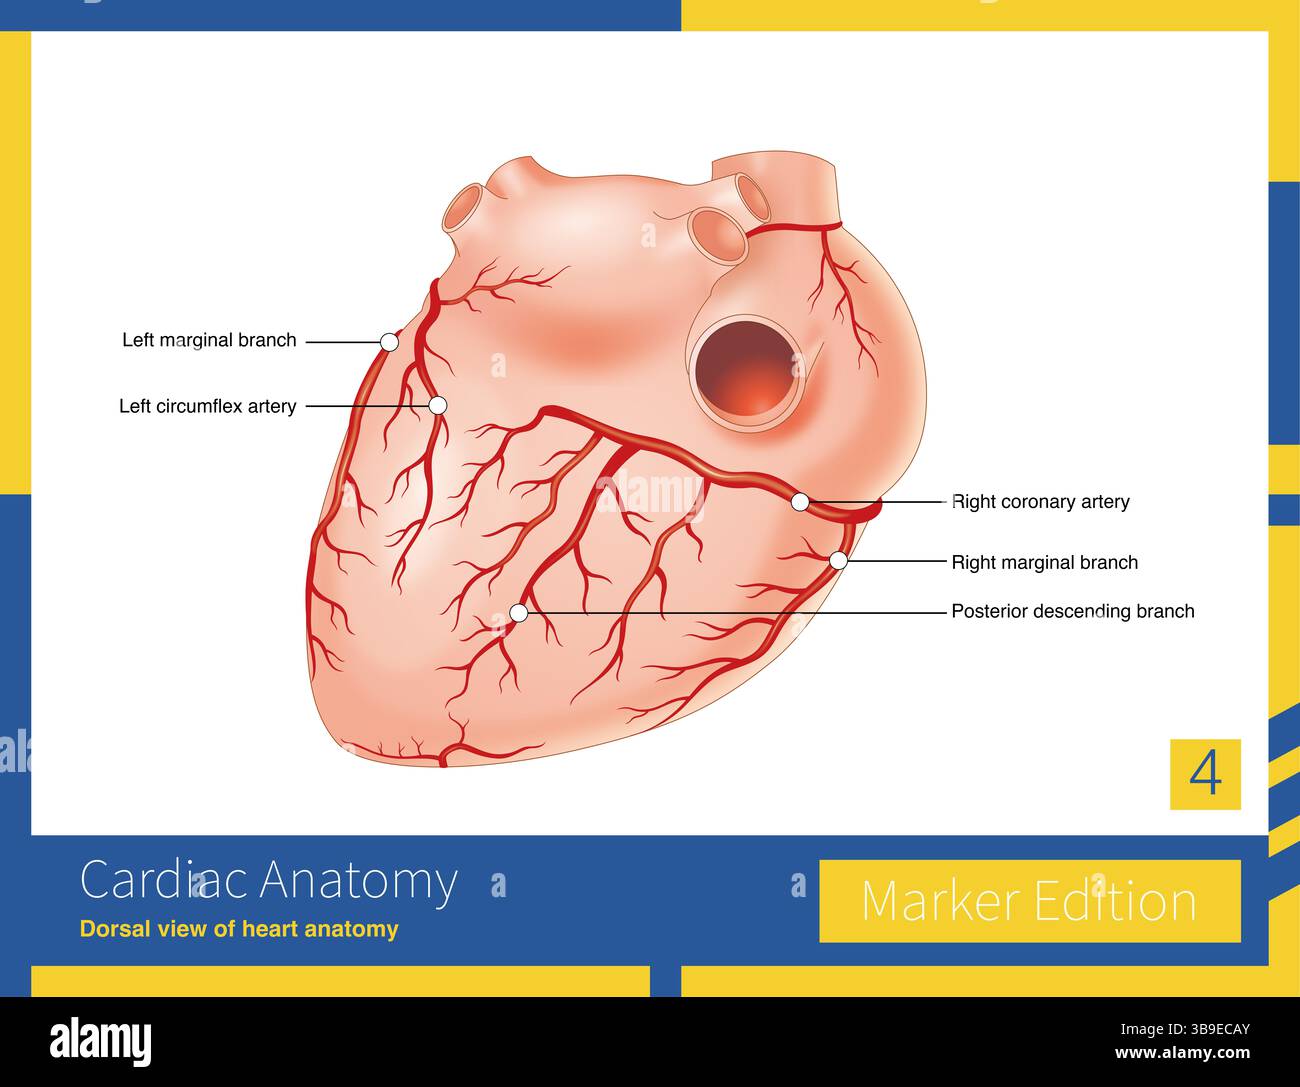

Most individuals have a dominant distribution of the right coronary artery, which sends out the posterior descending branch to supply the posterior in Stock Photohttps://www.alamy.com/image-license-details/?v=1https://www.alamy.com/most-individuals-have-a-dominant-distribution-of-the-right-coronary-artery-which-sends-out-the-posterior-descending-branch-to-supply-the-posterior-in-image677053299.html

Most individuals have a dominant distribution of the right coronary artery, which sends out the posterior descending branch to supply the posterior in Stock Photohttps://www.alamy.com/image-license-details/?v=1https://www.alamy.com/most-individuals-have-a-dominant-distribution-of-the-right-coronary-artery-which-sends-out-the-posterior-descending-branch-to-supply-the-posterior-in-image677053299.htmlRM3B9ECAY–Most individuals have a dominant distribution of the right coronary artery, which sends out the posterior descending branch to supply the posterior in